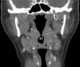

Lingual tonsil

The lingual tonsils are a collection of lymphatic tissue located in the lamina propria of the root of the tongue. This lymphatic tissue consists of the lymphatic nodules rich in cells of the immune system (immunocytes). [Source: Wikipedia ]